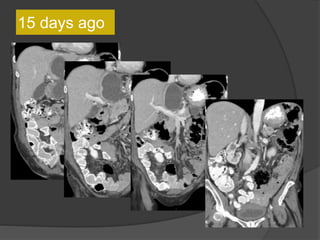

Case 1: 64F, abdominal distention, pain, h/o

SBO

Axial CT images

Coronal images

15 days ago

This lesion is larger compared to the CT 15 days

ago

• Multilobulated thick-walled cystic lesion in the lesser sac and extending along the

adjacent peritoneal spaces and gastrohepatic ligament. Cystic lesion in the left

hemipelvis

• Minimal ascites, omental and mesenteric thickening

Present exam 15 days ago

Increased size

15 days

Present exam

Case 1 Diagnosis: Recurrent metastatic disease

with mucinous ovarian tumor